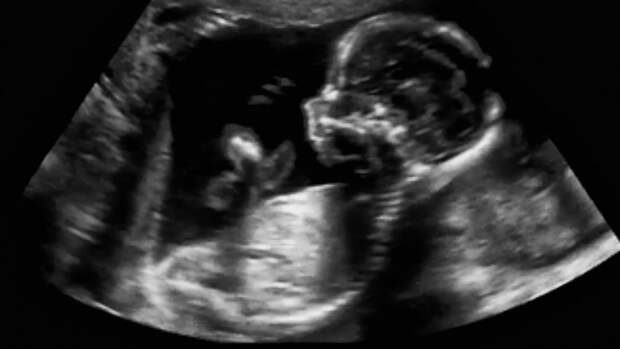

Люди с этим синдромом имеют родовые пути и матку, но у них нет функционирующих яичников, поэтому иметь детей они могут только после ЭКО с донорской яйцеклеткой. Такая особенность также располагает к развитию редких форм рака.Исследователи сосредоточились на изучении участка ДНК Y-хромосомы SRY, именно он определяет мужской пол будущего человека.